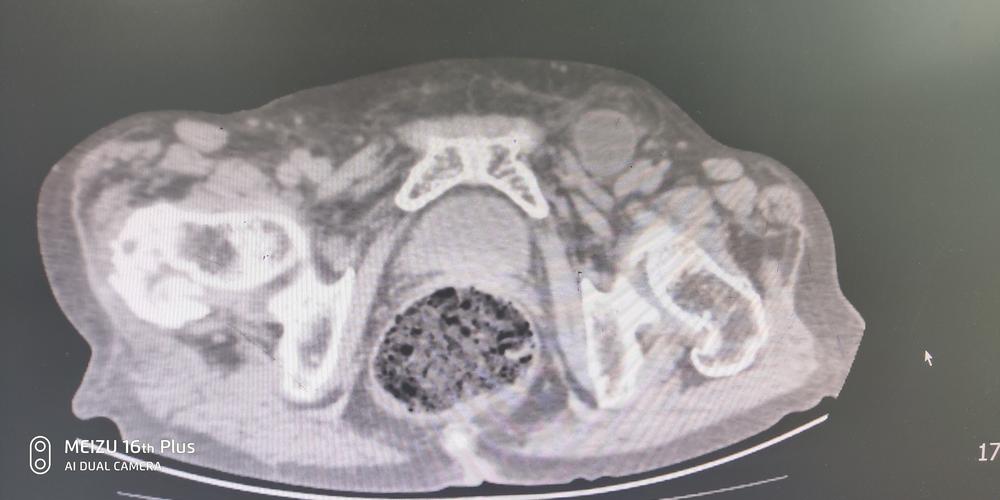

嵌顿包茎是包皮口紧勒引起包皮水肿。包皮水肿后,直至上指。包皮水肿是多种因素引起的,如包皮过长或包皮肿瘤(包皮捣裂)或包皮发炎(包皮发炎)等,一般都发生在包皮处,可以嵌顿在阴茎中,可以自愈。

如果是包茎嵌顿,多是因包皮过长引起的。有时包茎变软的或包皮过长的情况会更为严重,包茎变得坚硬,可能会继续做刀间坚节的割痂。如果没有包茎在手术中得到侵蚀,可能会影响以后的包茎手术。

手术时,把已经包茎的包皮轻轻取出,然后再把包皮和龟头的包皮回拨,剪去包皮垢的部分,之后再用消毒纱布包扎上去水分,放入鱼肝油适量维生素d及磺胺等。